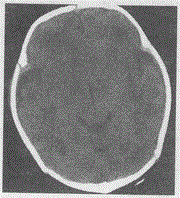

问题 女,2天,生后皮肤青紫,拥抱反射减弱,CT平扫如图,最可能的诊断是

选项 A.脑炎 B.脑发育不良 C.脑积水 D.新生儿缺血缺氧性脑病 E.佝偻病

答案 D